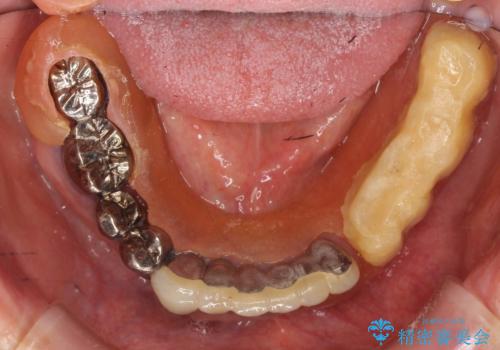

- 他院にて入れ歯を入れたが全体的に左に傾いており、咬みにくく、見た目も気になるといらっしゃった方の症例です。

診査の結果、虫歯が進行し保存できない歯が多かったため抜歯し、磁性アタッチメントを用いたインプラントオーバーデンチャーによる咬合及び見た目の改善を行いました。

磁性アタッチメントとは残っている歯根またはインプラントに磁性金属を埋め込み、入れ歯の裏側(歯肉に触れる側)に小さい磁石を埋め込んで固定させる入れ歯(義歯)のことです。土台となる歯やインプラントに無理な負荷をかけず、磁力によって強力に密着するため、ぐらついたり、ズレたりすることはありません。また総入れ歯だけでなく部分入れ歯にも使用できます。